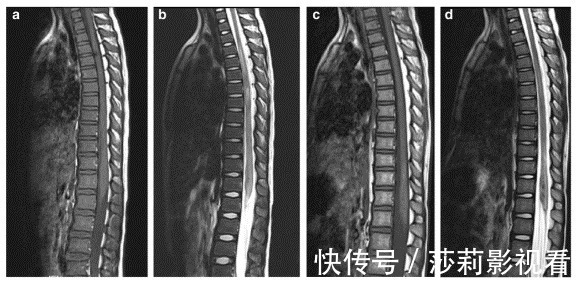

其实并不是,只是在医院看到了太多瘫痪的孩子,他们当中很多都是因为学舞蹈导致的脊髓损伤。舞蹈跟脊髓的损伤,看似没什么关系啊,怎么就联系到一起了?好好的孩子,咋就脊髓损伤了?说起脊柱损伤,大家的第一反应就是瘫痪,这确实是急剧损伤导致的最严重后果。很多人以为脊髓损伤只是出现在成人当中,可是儿童的脊髓损伤也是很常见的。有研究表明,儿童脊髓损伤占全部脊椎损伤的0.3%~9.47%。损伤原因是很多的,比如车祸、跌倒以及运动相关损伤。在国外最常见的原因就是车祸了,其次是高处坠落。特别是三岁以上的男孩,由于好动而且喜欢从事危险活动,所以在国外,三岁以上的男孩脊髓损伤人数明显高于女孩。可是我们国家不一样。在我国,儿童脊髓损伤最常见的原因是运动损伤。很多人好奇,明明是运动损伤,跟舞蹈有什么关系呢?其实在纳入研究分析的时候,舞蹈就是运动的一种。另外,国外的研究当中颈部的颈椎损伤是高发部位达到87.19%。和国外不一样的是,我国更多见的是胸髓损伤,达到了75.8%。

特别是最近几年,舞蹈练习越来越多了,儿童因此所获得的脊髓损伤也屡见不鲜。相信你一定看过类似的新闻。而更为可怕的是因为儿童生长发育的特点,脊髓损伤的治疗通常是比较困难的。哪个动作最伤脊髓?孩子就算学舞蹈,最好也别学需要下腰的舞蹈。很多牵拉伤都见于舞蹈的下腰动作。曾经有学者回顾了12名舞蹈导致的损伤,发现他们损伤的原因无一例外全都是因为做了这个下腰动作。

正常发育中的神经根,在椎管内向下数节段后,通过对应的椎间孔穿出。但是在做下腰动作的时候,神经相对固定,但是随着脊柱向后过伸脊髓就非常容易被轴向牵拉。1、脊柱过伸的时候,棘间韧带向前突出,椎管同时变窄。2、脊髓随着脊柱节段间距离变短而出现缩短增厚。3、前纵韧带的撕裂,椎间盘和终板之间的剪切力作用,这些都可以导致椎体过度向后移位,最后导致脊髓受压。这也是在下腰动作时,孩子脊髓非常容易受损伤的原因。

另外在儿童发育的过程当中,脊柱的发育并没有完全成熟,也有自身的形态特点,比如椎体前部呈楔形,非常容易产生相邻两椎体间的滑动。同时孩子的脊髓非常不耐受牵拉,新生儿的脊柱可以承受5厘米牵拉,而且不出现损伤。但他的脊髓仅仅承受0.635厘米的牵拉就会出现断裂。特别是在胸椎第4节到第9节,椎管是最窄的,而且胸髓又细又长,血液供应十分不好。可以说,任何造成节段动脉痉挛或者卡压的因素,都会导致脊髓缺血,最终出现脊髓损伤。